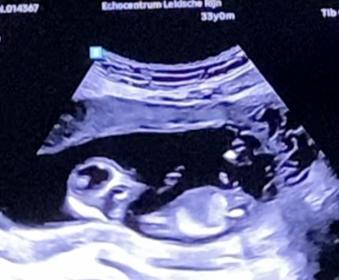

Tricky NUB 13+1 weeks? Long NUB but some stacking?

I had a scan yesterday (13+1 weeks!). During the scan I was convinced I saw long somewhat flat, but also a stacked nub (I saw a shadow in the background), but the tech said it was the stacking was the umbilical cord. The tech said she saw a flat NUB that I is why she was leaning more towards girl.

I posted my scans online and got mostly boy guesses (some girl because of the "flat" NUB) but I was wondering if it's still possible it might be a girl? That the "stacked thing" is something else??? (Already got 3 boys so a girl would be so welcome!)